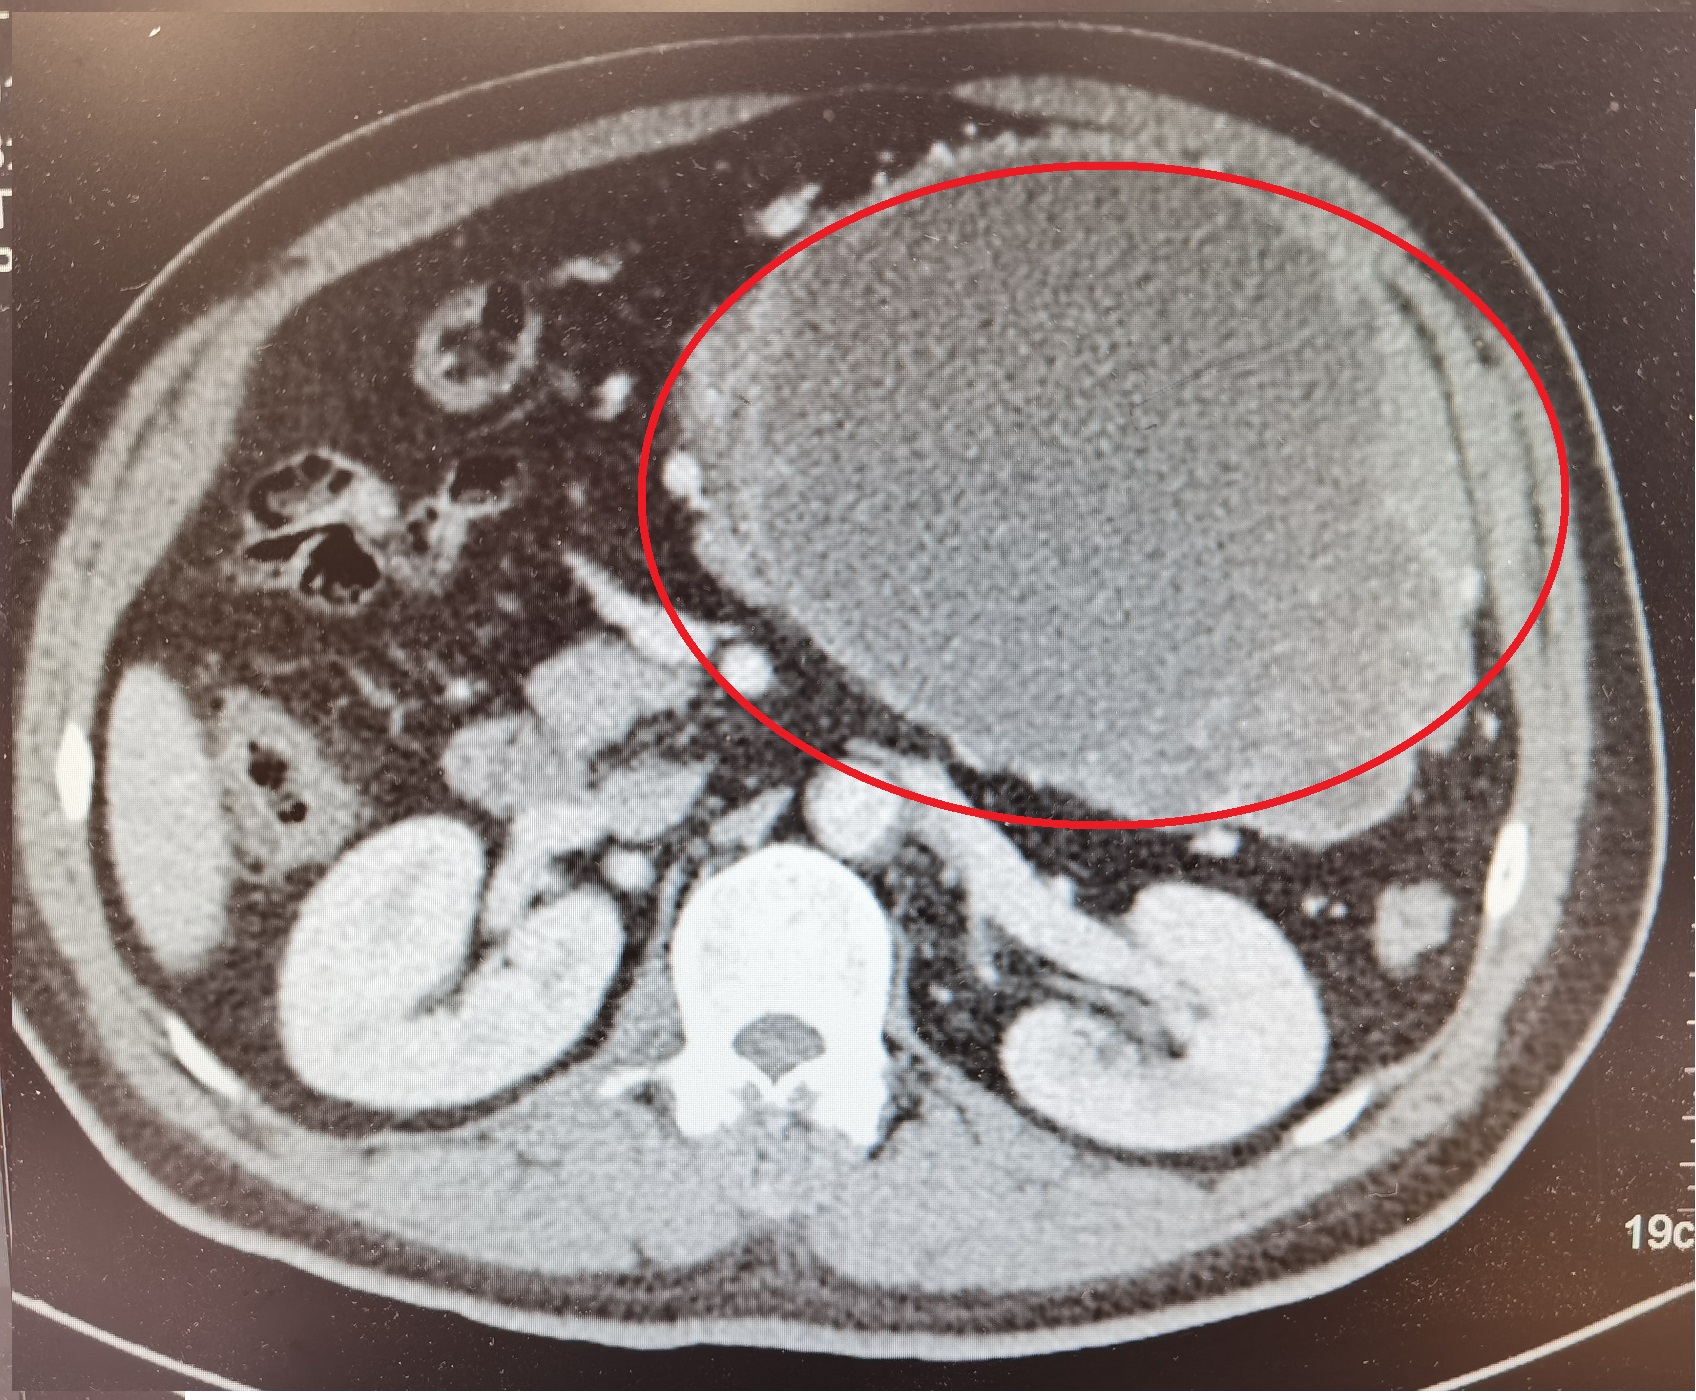

病例情况:患者男性,58岁,因“上腹部隐痛半月余”于2015-08-20入院。患者于入院半个月前开始出现上腹部隐痛,进食后明显,自服护胃药物后稍缓解,无发热、恶心呕吐。查体:左上腹可触及巨大包块,大小约15×20cm,质硬,边缘不清,表面尚光滑,固定,有轻压痛,无反跳痛。肝脾肋下未及,肝肾区无叩击痛,移动性浊音阴性,肠鸣音正常。胸腹部增强CT:1.左上腹巨大占位病变(11.7×15.1×21.3cm),与胃、降结肠、横结肠及胰腺分界欠清,考虑胃肠道间质瘤可能;胃镜:1.慢性非萎缩性胃炎伴糜烂;2.胃多发隆起肿物(间质瘤?)。初步诊断:腹部巨大肿物,胃间质瘤可能。

术前腹部CT:左上腹巨大肿块